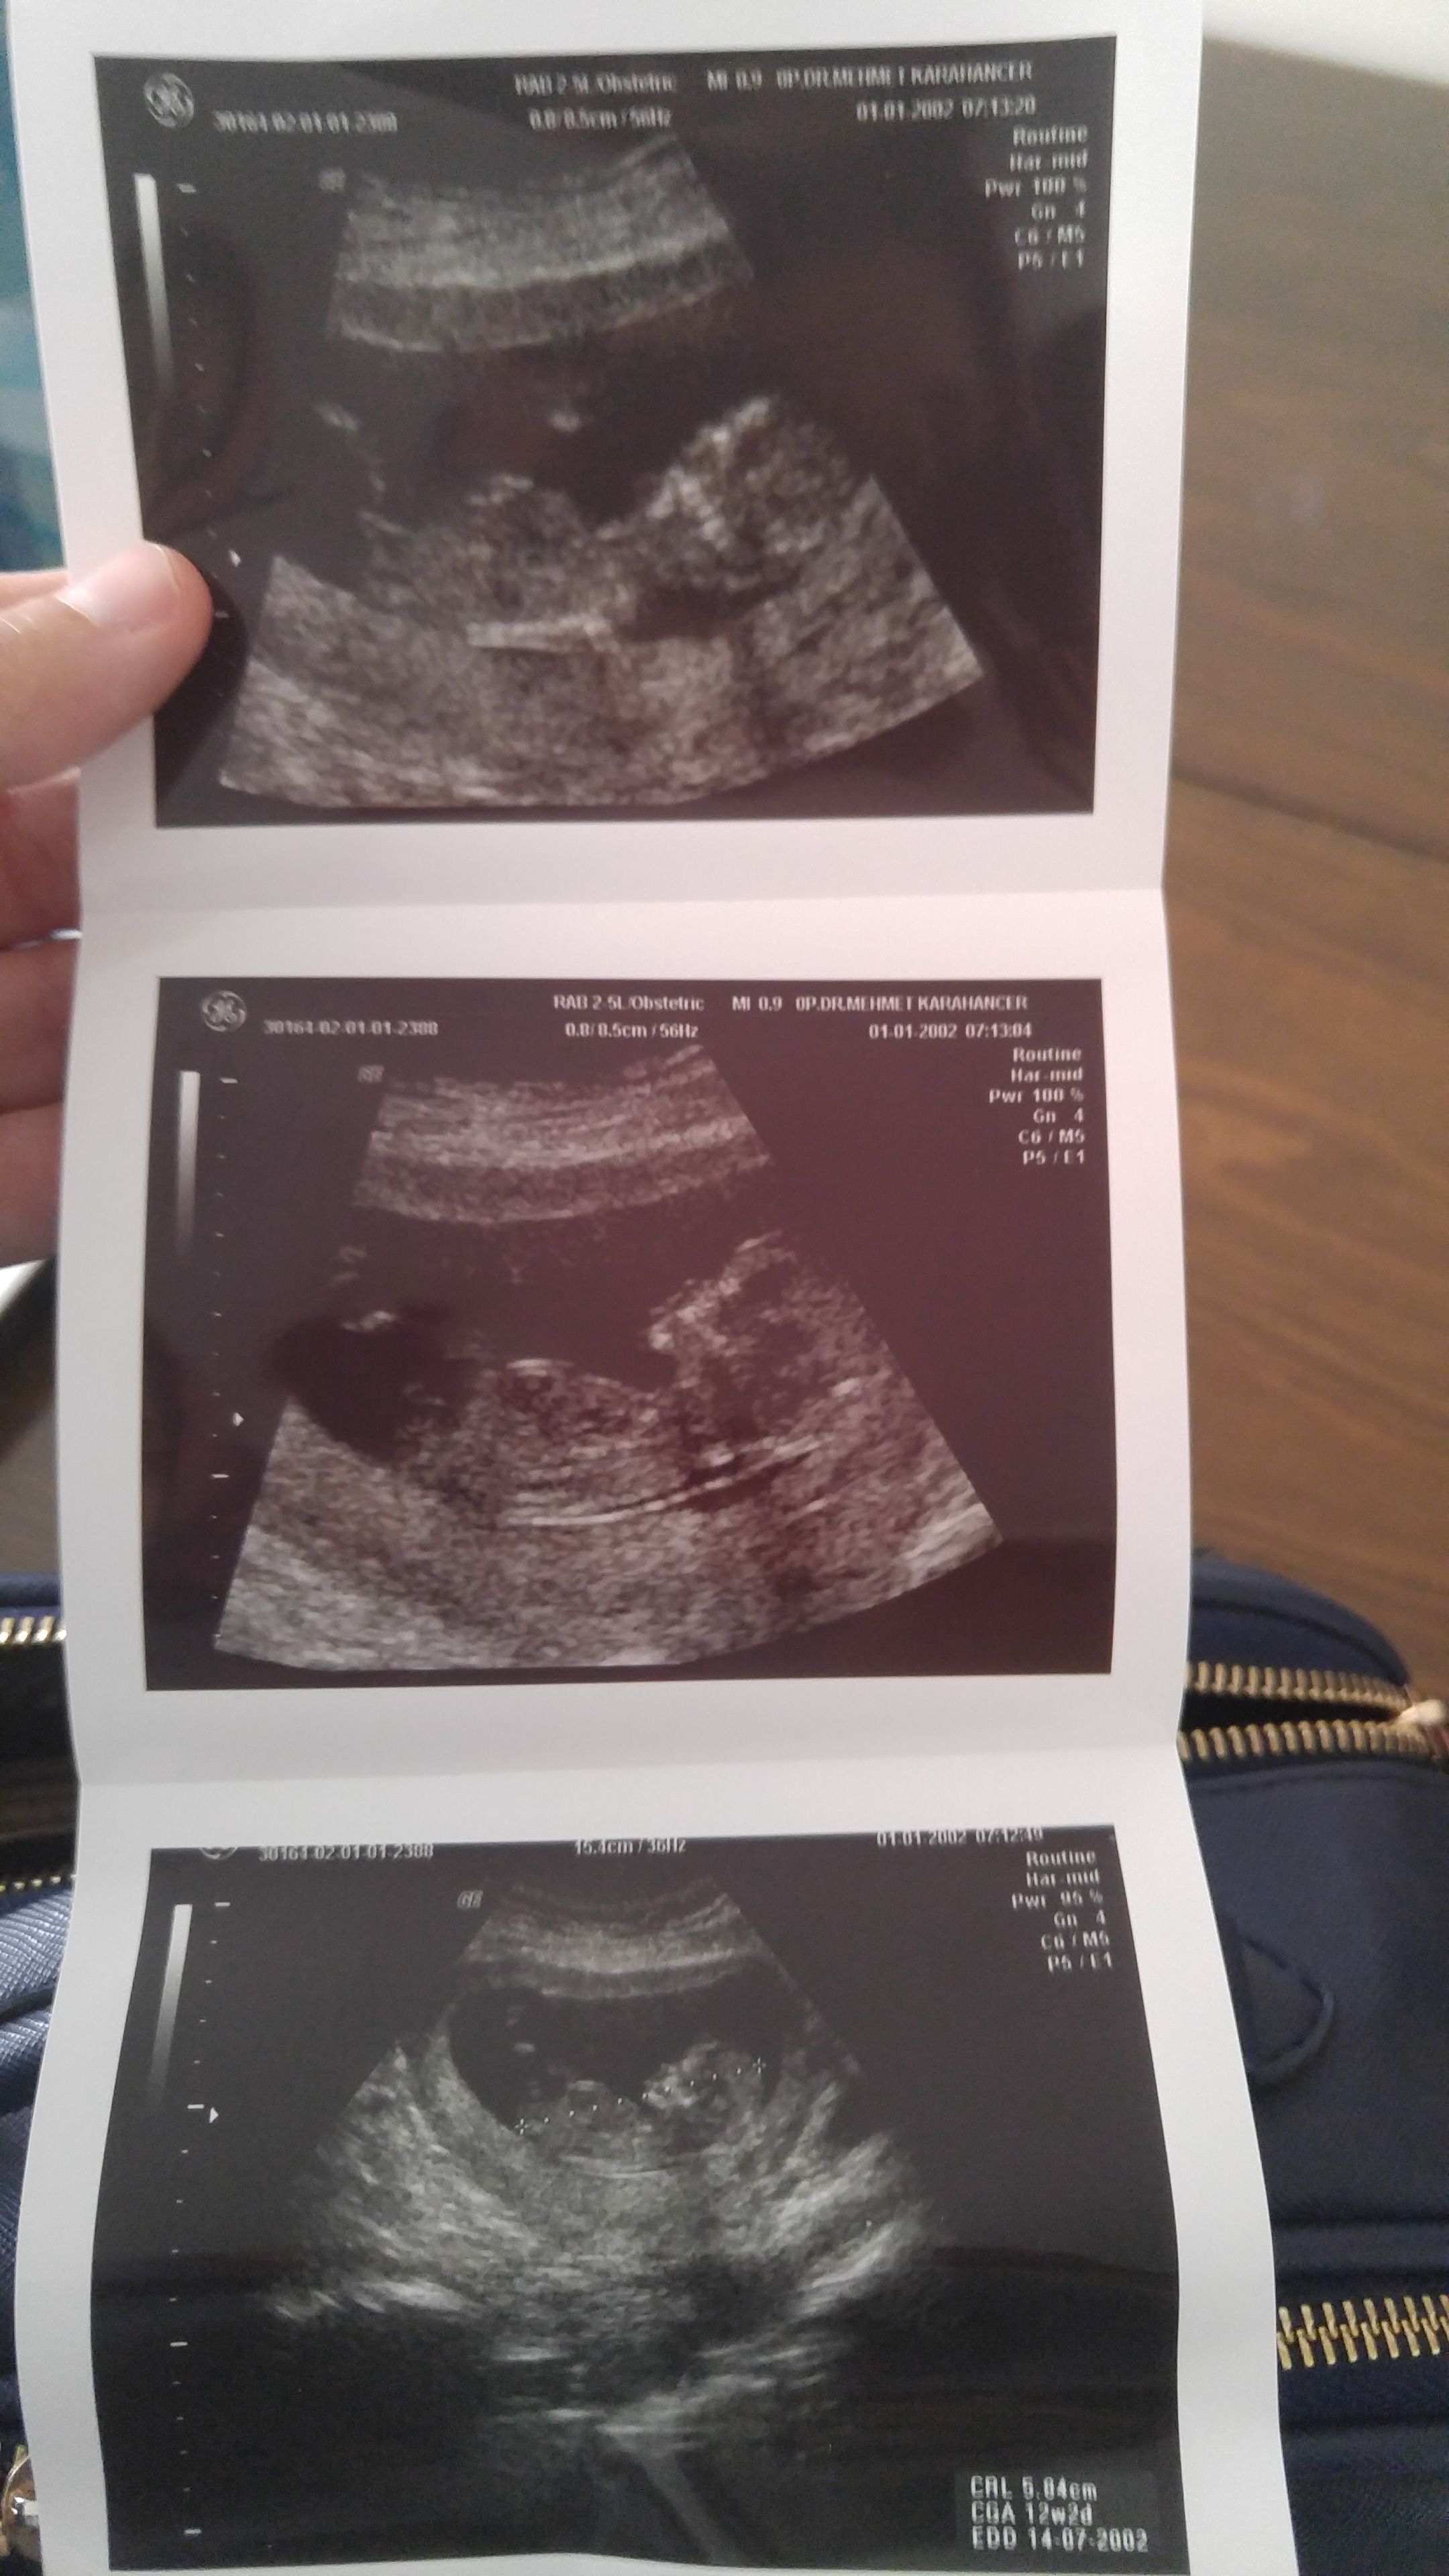

HemşireniZ Aktif Üye Üye 2 Mayıs 2017 #273 Merhaba emin olmamakla birlikte bebeğinizin cinsiyetinin erkek olduğunu düşünüyorum.Sağlıklı gebelik geçirmeniz dileği ile.

Merhaba emin olmamakla birlikte bebeğinizin cinsiyetinin erkek olduğunu düşünüyorum.Sağlıklı gebelik geçirmeniz dileği ile.